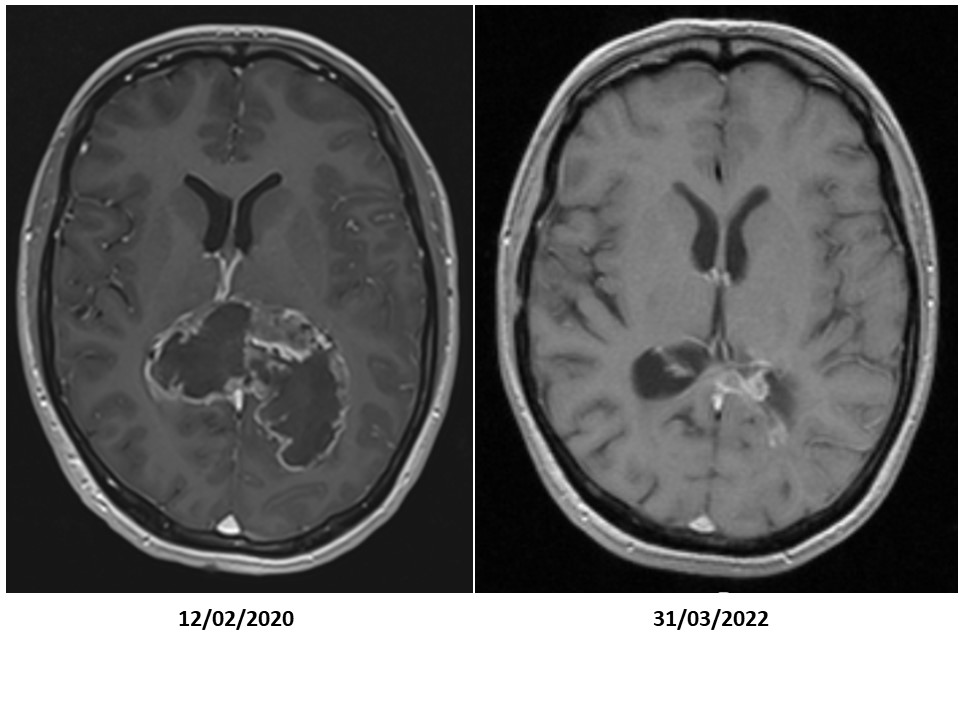

Neurosurgery and radiochemotherapy are primarily aimed to reduce the tumour volume. Maintenance chemotherapy is aimed to keep control over residual tumour cells. We combined immunogenic cell death therapy (oncolytic virus therapy and modulated electrohyperthermia) during maintenance chemotherapy, and continued with active specific immunotherapy using dendritic cell vaccines and maintenance immunogenic cell death therapy, in combination with modulatory immunotherapy, to improve the overall survival of GBM patients.

To our surprise, a strong synergy became visible between the chemotherapy and the Individualised Multimodal Immunotherapy for the improvement of the overall survival for IDH1 wild-type MGMT promoter-unmethylated patients. Whereas both treatment modalities alone did hardly improve the median overall survival beyond 12 months as obtained with radiotherapy alone, the median overall survival with combination treatment raised to 22 months with a two-year overall survival of 36%. The combination treatment resulted in a median overall survival of 33 months for IDH1 wild-type MGMT promoter-methylated patients with a two-year overall survival of 82%.

To conclude, the role of the Individualised Multimodal Immunotherapy integrated within and after the standard of care to improve long-term overall survival with good quality of life of GBM patients becomes obvious. Immunogenic cell death therapy changes the tumour-host interaction by releasing danger signals within the tumour microenvironment and thereby starting an immunisation process. The dendritic cell vaccines are loaded with antigenic extracellular microvesicles and apoptotic bodies induced by immunogenic cell death therapy, and yielded out of the serum. In this way, the vaccine is loaded with actualised tumour antigens out of residual tumour cells that escaped the radio-chemotherapy and the maintenance chemotherapy. The maintenance immunogenic cell death therapy remains killing potentially appearing new tumour sub-clones thereby including potential novel tumour antigens under the dendritic cell vaccine-induced global anti-GBM immune protection. This treatment strategy is adapted for each patient and each phase of the disease, taking into account dynamic changes in the tumour, in the immune system, and in the tumour-host interaction.